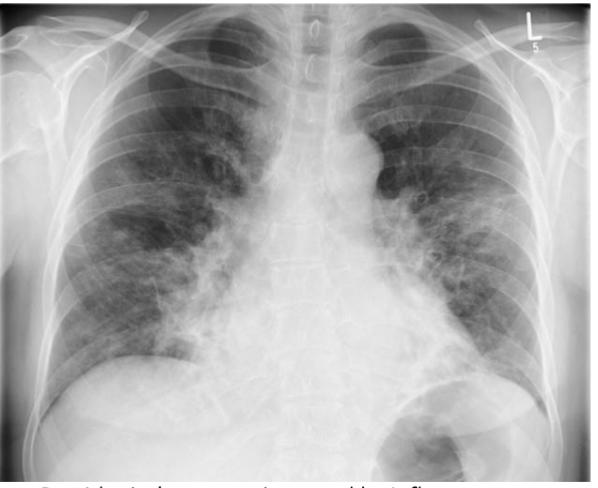

What is this? and what causes it?

air space filling w air bronchograms, PNA

viral pna caused by influenza